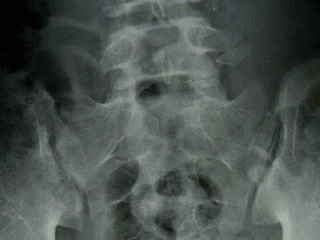

背骨の両脇にある筋肉(画像の茶色の部分)は、仙骨が出発点になっていますから、腰痛等で、それらの筋肉に障害が起こっている場合は、仙骨の痛みに繋がる可能性もあります。また、急に重い物を持ったり、高いところから飛び降りたりした場合は、仙腸関節(画像の丸の部分)が捻挫し、仙骨部に痛みを起こすこともあります。